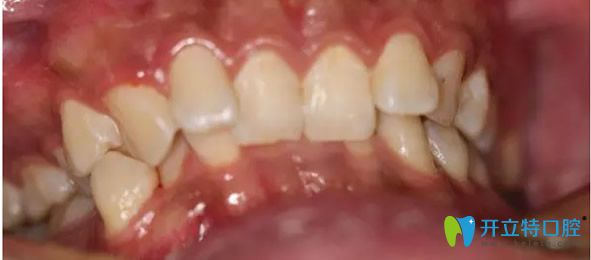

先看看我在武漢愛(ài)齒爾口腔矯正牙齒前的照片:

武漢愛(ài)齒爾口腔矯正牙齒前

到后,龐勇主任幫我做了牙齒CT,發(fā)現(xiàn)我牙齒不齊且伴有深覆合現(xiàn)象,很影響美觀。但我又不愿意拔牙矯正。醫(yī)生就為我制定了3M自鎖托槽矯正牙齒的方案。于是我的正畸之路就開(kāi)始了。